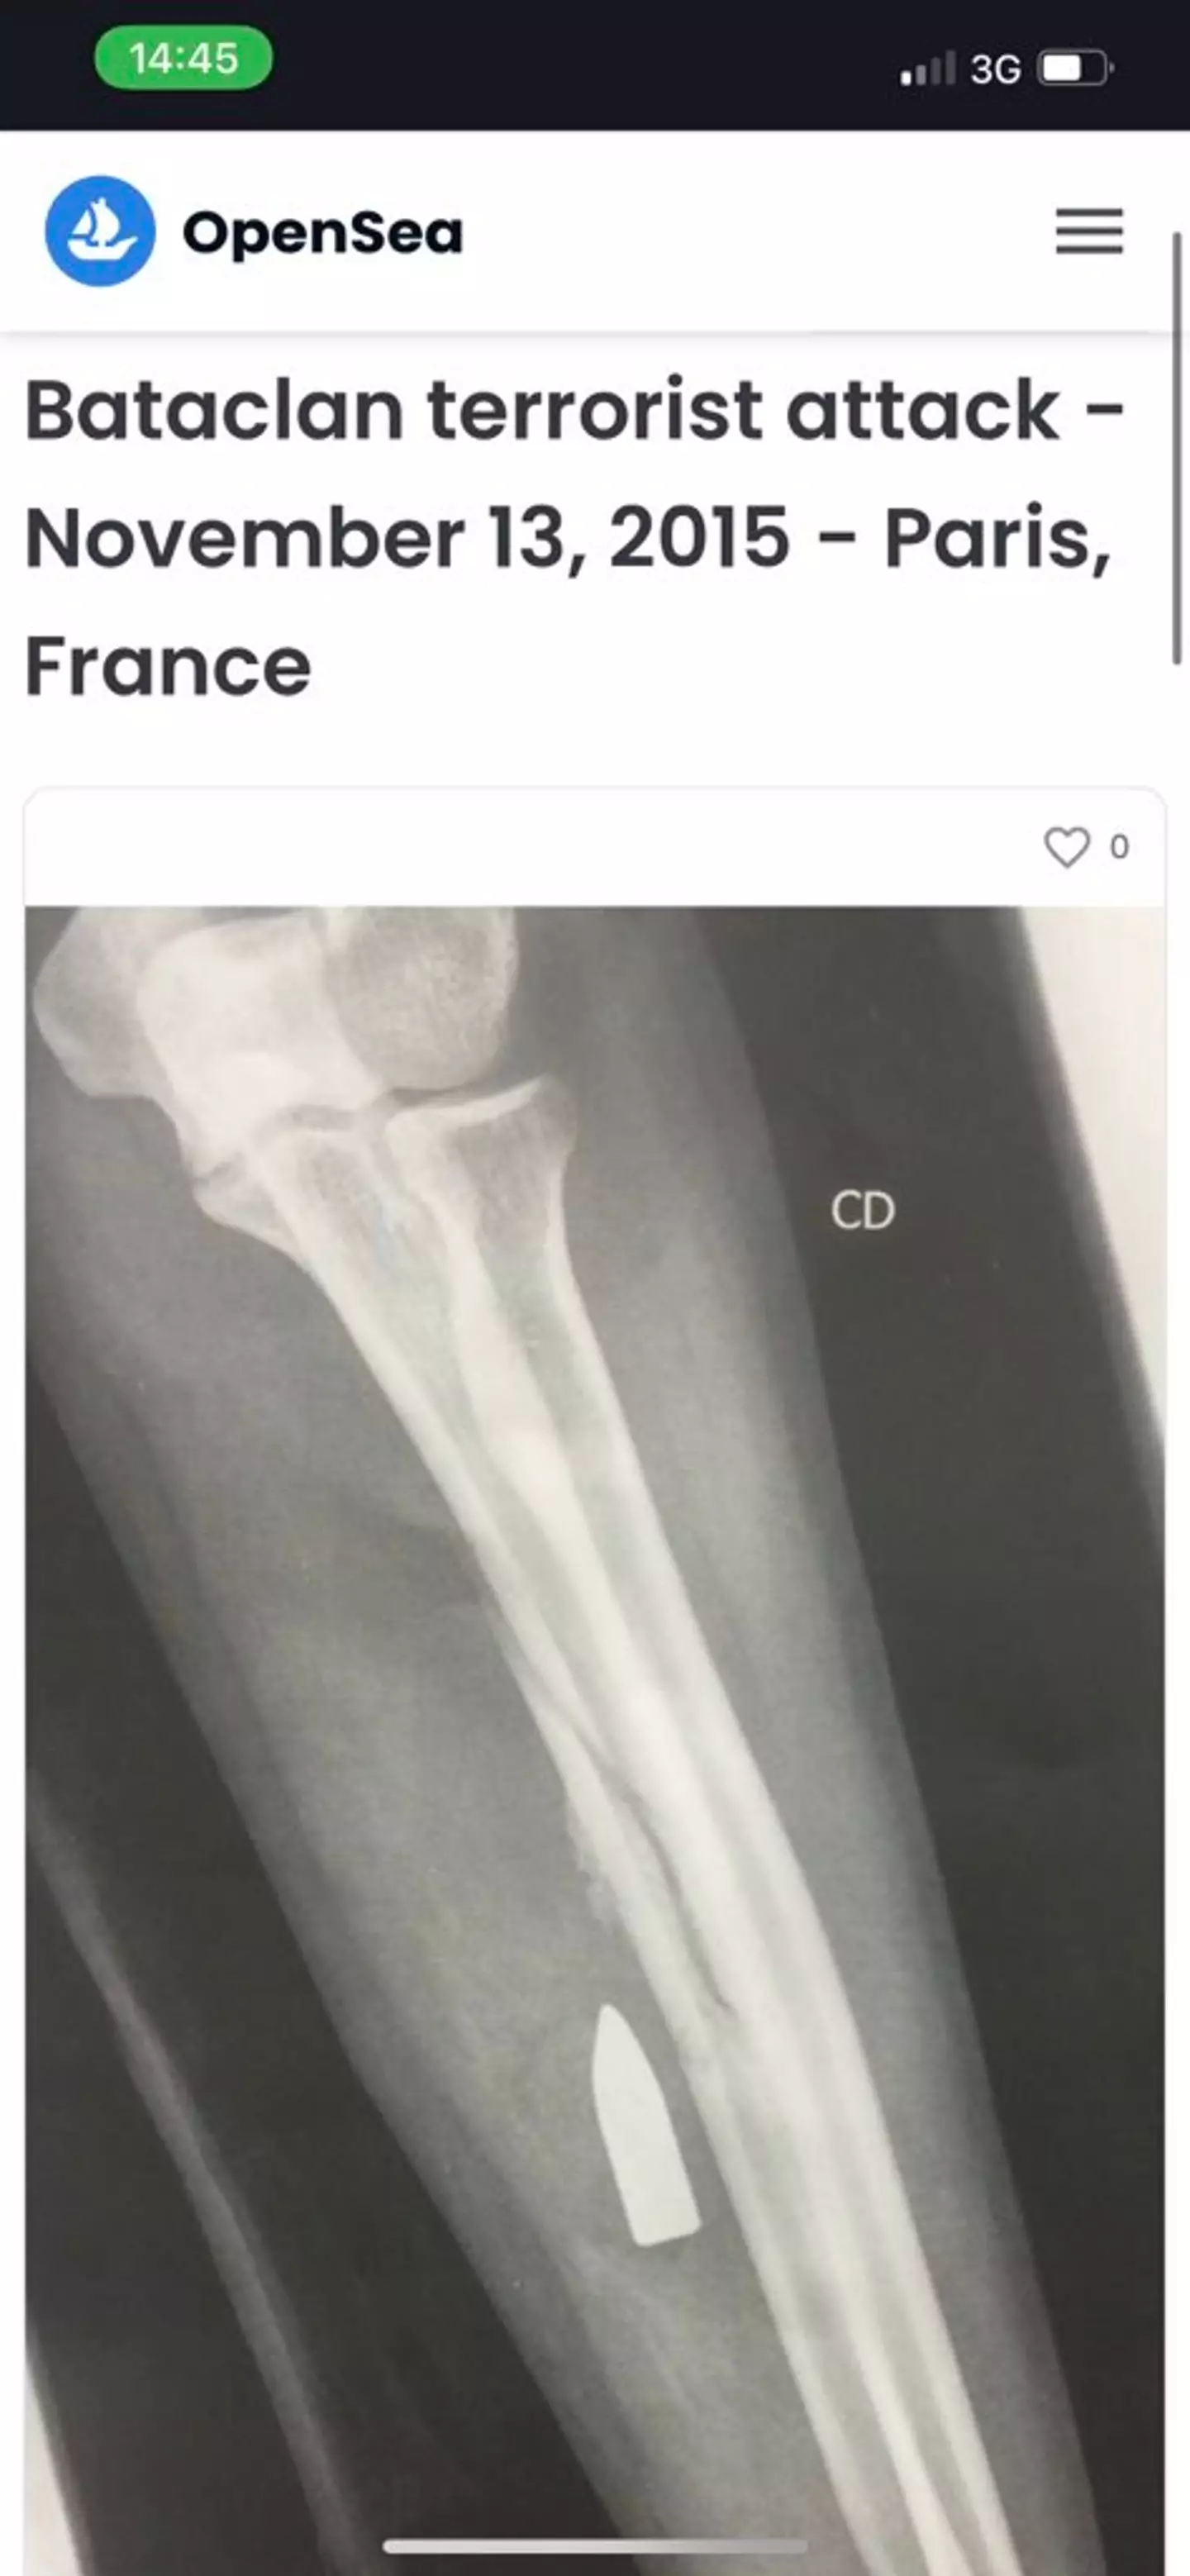

Although the Bataclan music hall victim can’t be identified from the still, the X-ray showed their forearm with a bullet still lodged inside.

The Open Sea listing, which the doctor wrote beside the X-ray, detailed private information of his patient, including her gender, her relationship status at the time, and where the incident took place. It also noted her diagnosis following the shooting.